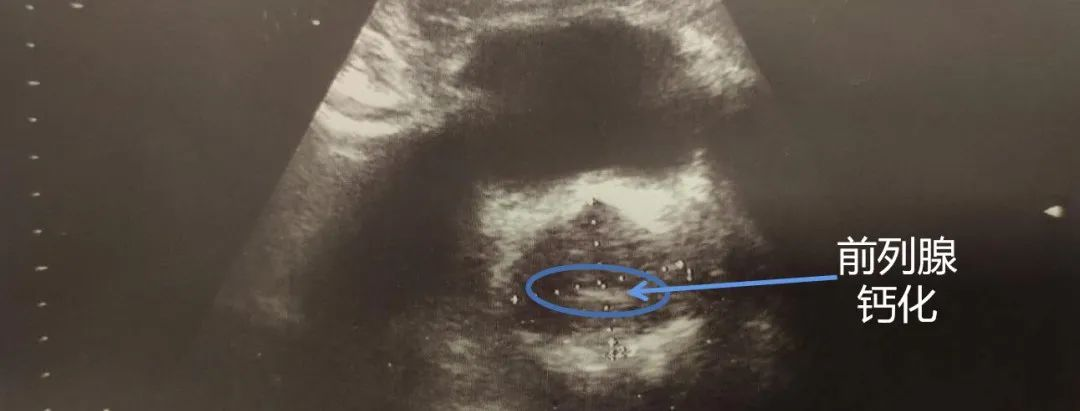

但好在绝大多数前列腺炎患者的症状都不重,甚至很轻微,乃至相当一部分患者直至体检发现了前列腺钙化才知道前列腺中已存在炎症。